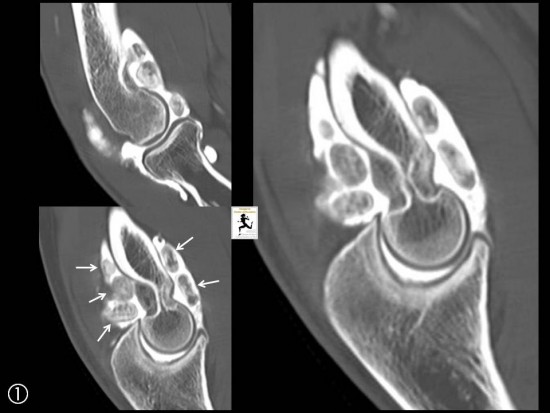

ARTHRO-SCANNER ET ARTHRO-IRM

Nodules moulés

Lésions (cartilages, tendons, ligaments…)